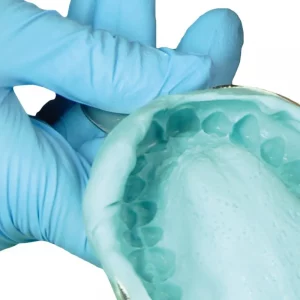

API Acrylic Teeth Sets – NewDent B2 (Pack of 4 Sets)

The api acrylic teeth sets by newdent are high-quality dental prosthetic teeth used in the fabrication of dentures. These teeth are made from durable acrylic material and are designed to replicate the appearance of natural teeth. They are available in various shades and sizes to match individual patient needs. The api acrylic teeth set to provide excellent aesthetics and functionality, making them a reliable choice for denture fabrication. New dent artificial teeth double layer acrylic teeth are a type of dental prostheses or dentures that are constructed with a two-layer structure made from acrylic resin. These teeth are designed to mimic the appearance, feel, and function of natural teeth, which makes them a popular choice among dental patients who have lost some or all of their natural teeth.

- Suitable for Full, partial, and skeletal dental prosthesis.